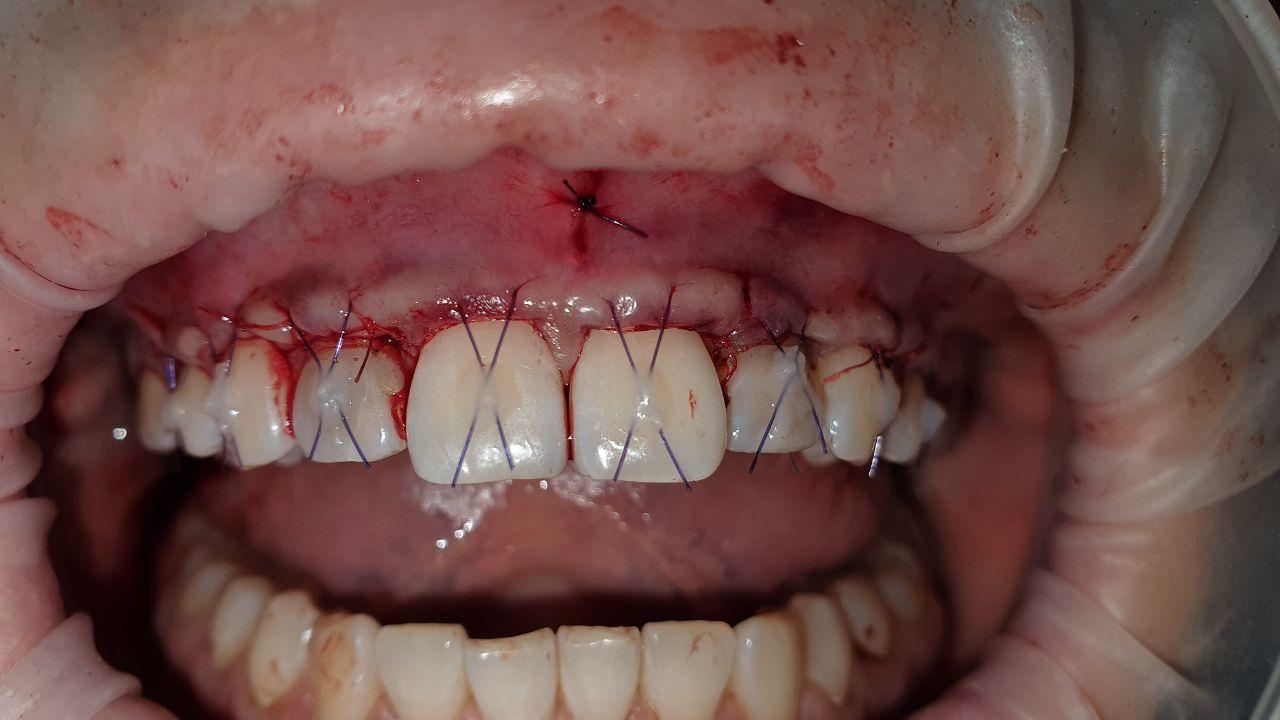

- проведение лоскутной операции

Кюретаж пародонтальных карманов- процедура по удалению поддесневых зубных отложений (т.е. микробного налета) с последующим сглаживанием поверхности корня, которая способствует восстановлению прикрепления десны к корню зуба. Чаще, процедура проводится под анестезией. Для поддержания здоровья десен процедуру необходимо проводить раз в 6 месяцев.

При необходимости